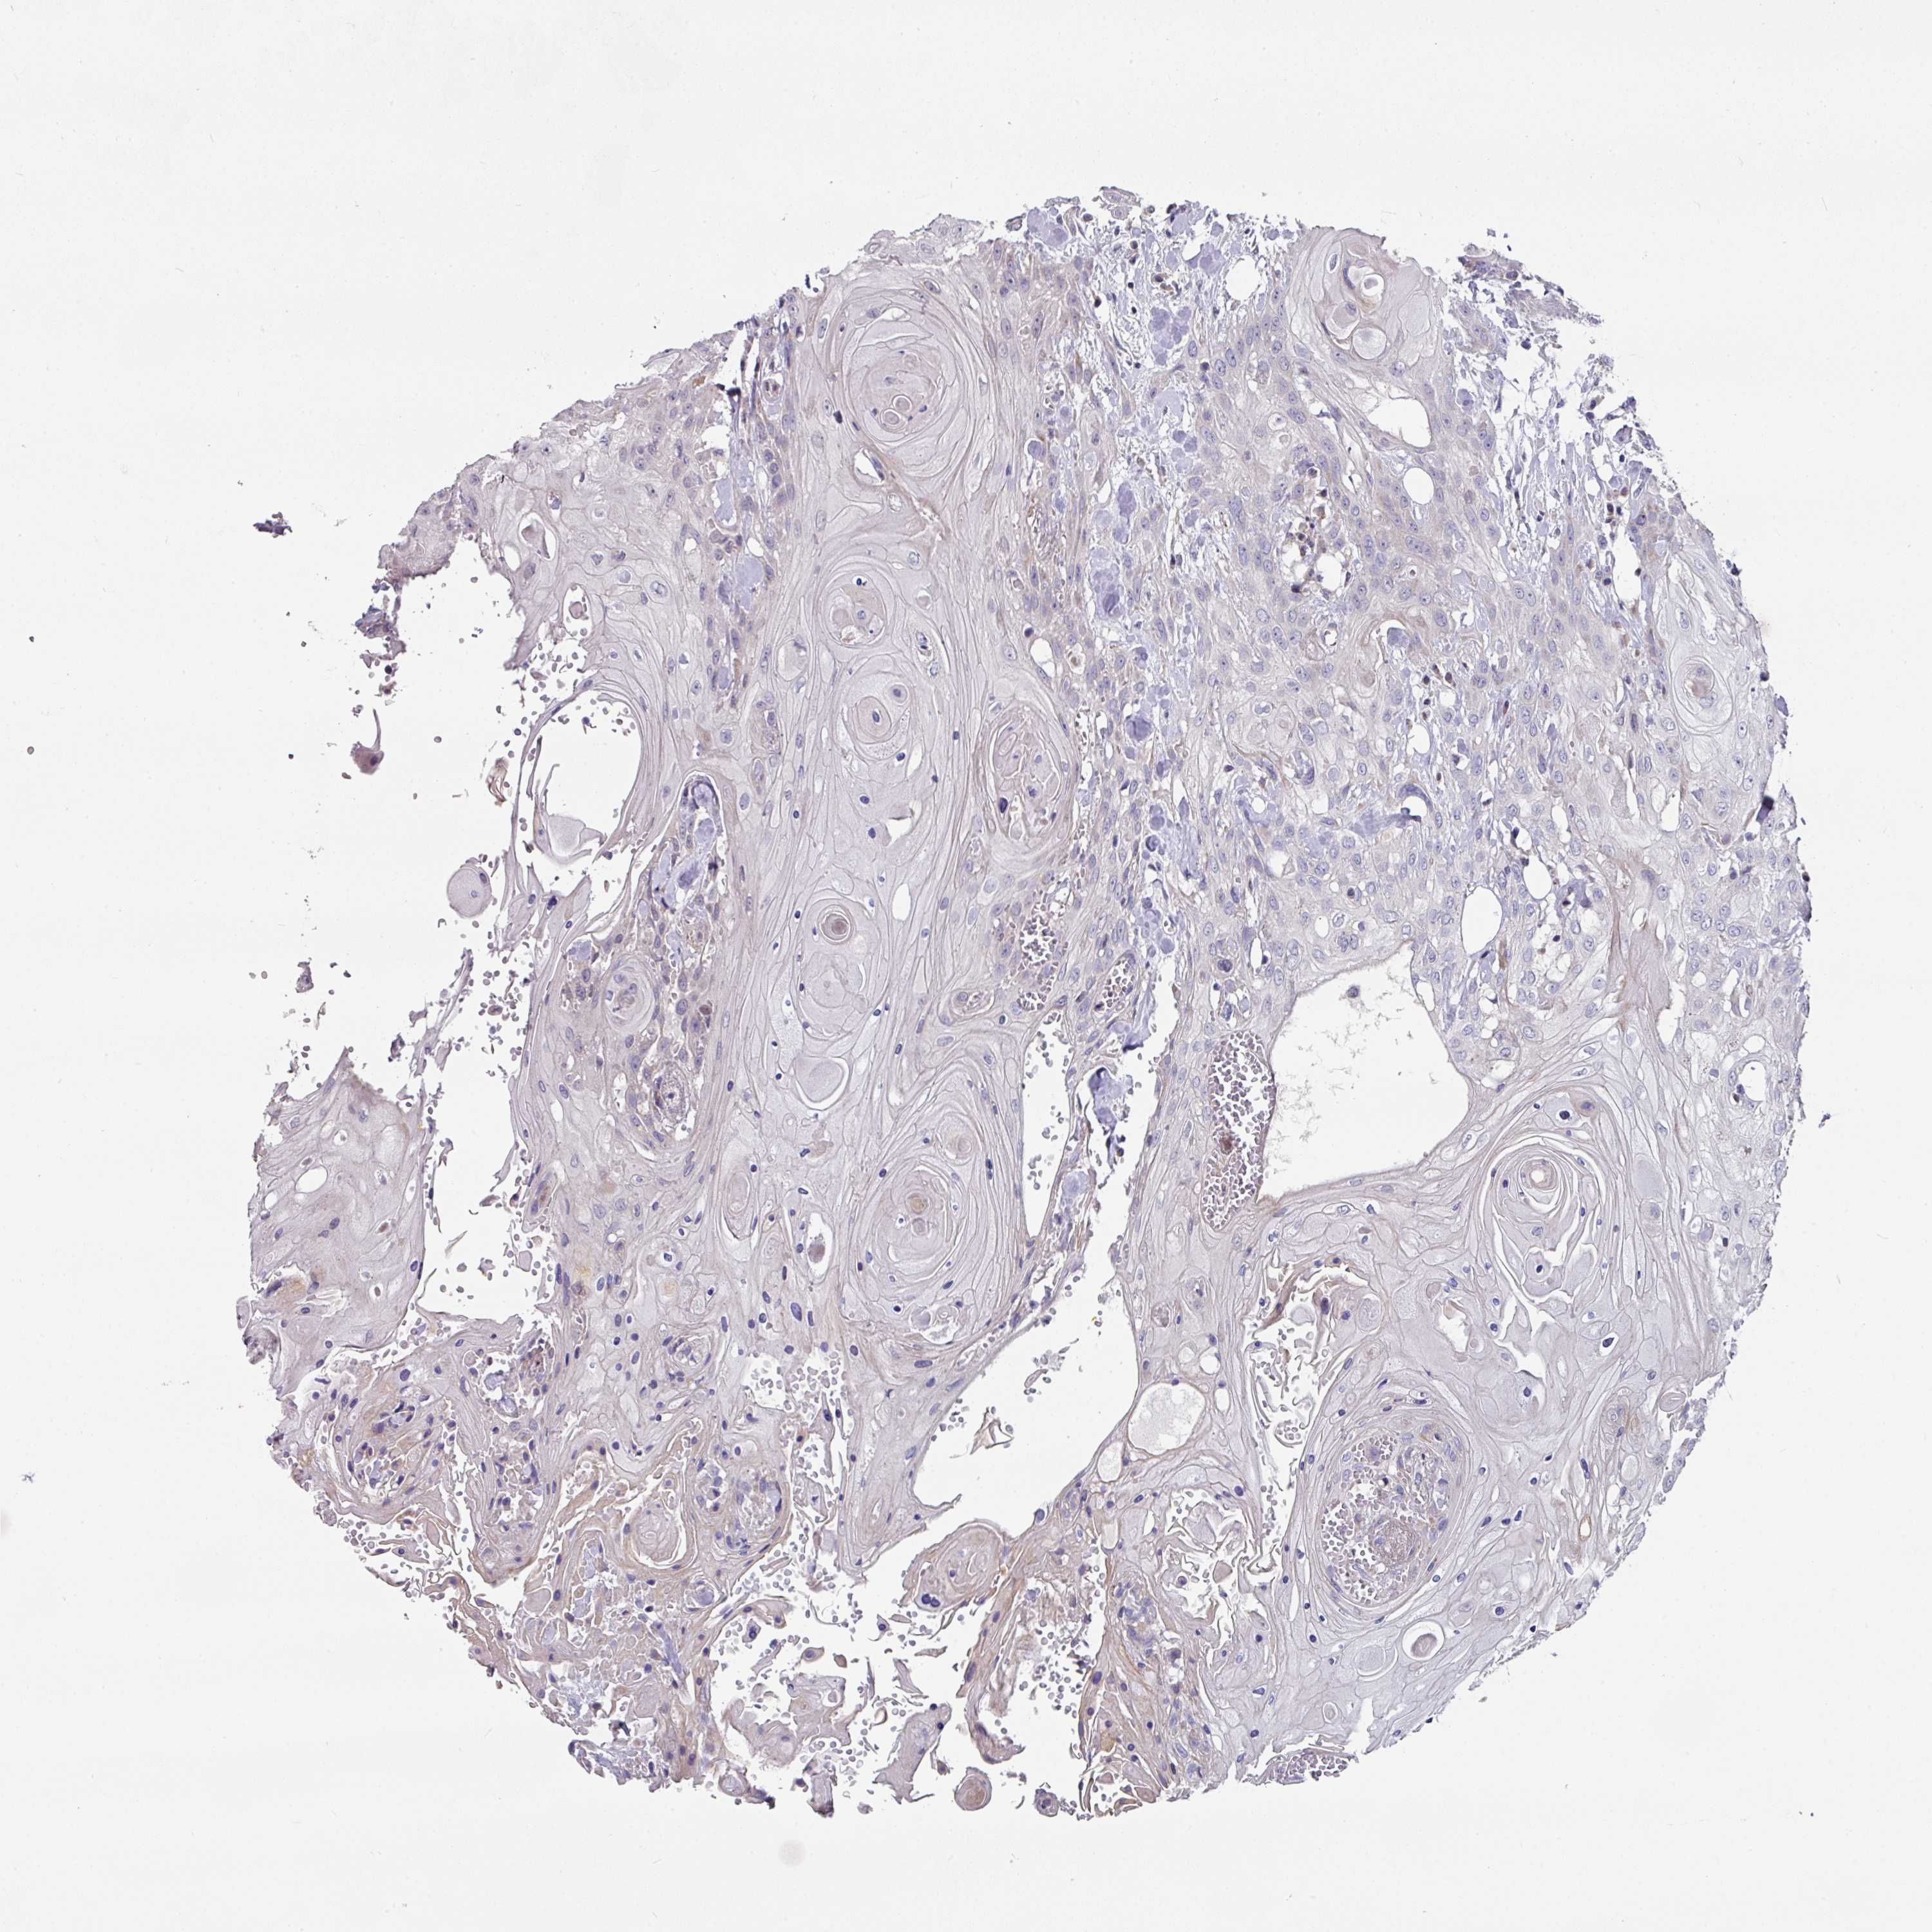

HEAD AND NECK CANCER - Protein expressioni

A mouse-over function shows sample information and annotation data. Click on an image to view it in a full screen mode. Samples can be filtered based on level of antibody staining by selecting one or several of the following categories: high, medium, low and not detected. The assay and annotation is described here.

Antibody stainingi

Antibody staining in the annotated cell types in the current human tissue is reported as not detected, low, medium, or high, based on conventional immunohistochemistry profiling in selected tissues. This score is based on the combination of the staining intensity and fraction of stained cells.

Each image is clickable and will lead to virtual microscopy that enables deeper exploration of all samples and also displays staining intensity scores, fraction scores and subcellular localization as well as patient and tissue information for each sample.

Antibody HPA048677

Antibody HPA056480

Antibody CAB011574

Staining

High

Medium

Low

Not detected

Intensity

Strong

Moderate

Weak

Negative

Quantity

>75%

75%-25%

<25%

None

Location

Nuclear

Cytoplasmic/membranous

Cytoplasmic/membranous,nuclear

Adenocarcinoma, NOS

Squamous cell carcinoma, NOS

Squamous cell carcinoma, metastatic, NOS

Adenoma, NOS